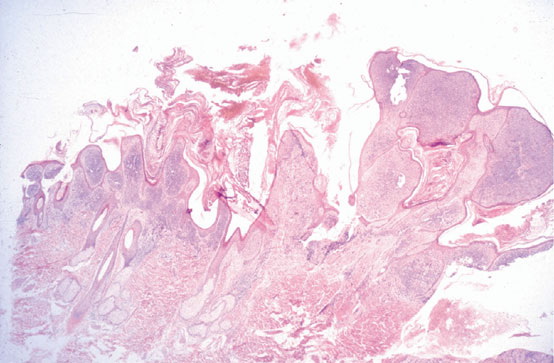

Verrucous melanoma = الميلانوم المتثألل